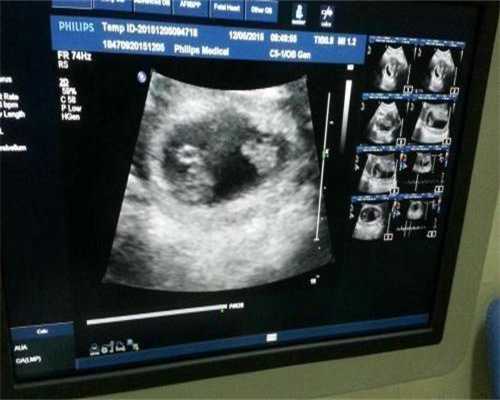

因为鲜胚移植是需要两天后才会开始着床,而囊胚移植后是移植当天就可以开始着床了,所以鲜胚移植到女性体内后,移植的第二天胎停正在发育形成囊胚,囊胚移植到女性体内后,会在移植后的第二天继续着床。

一般鲜胚移植到女性体内不会马上着床,一般情况下都需要两天后才开始着床,我们要知道,胚胎在着床过程中都是游离状态。鲜胚移植的第二天还不算是游离状态,因为需要先形成囊胚。如果患者有其他疑问可以随时咨询优先顾问,优选试管顾问将为您提供最专业的的解答!